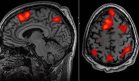

La musicoterapia se presenta como una intervención eficaz para mitigar estos síntomas. Emmanuel Ben, neuropsicólogo y músico, explicó que la música tiene la capacidad de activar zonas neuronales específicas en el cerebro de las personas con demencia, particularmente en el sistema límbico, que regula las emociones y la memoria.